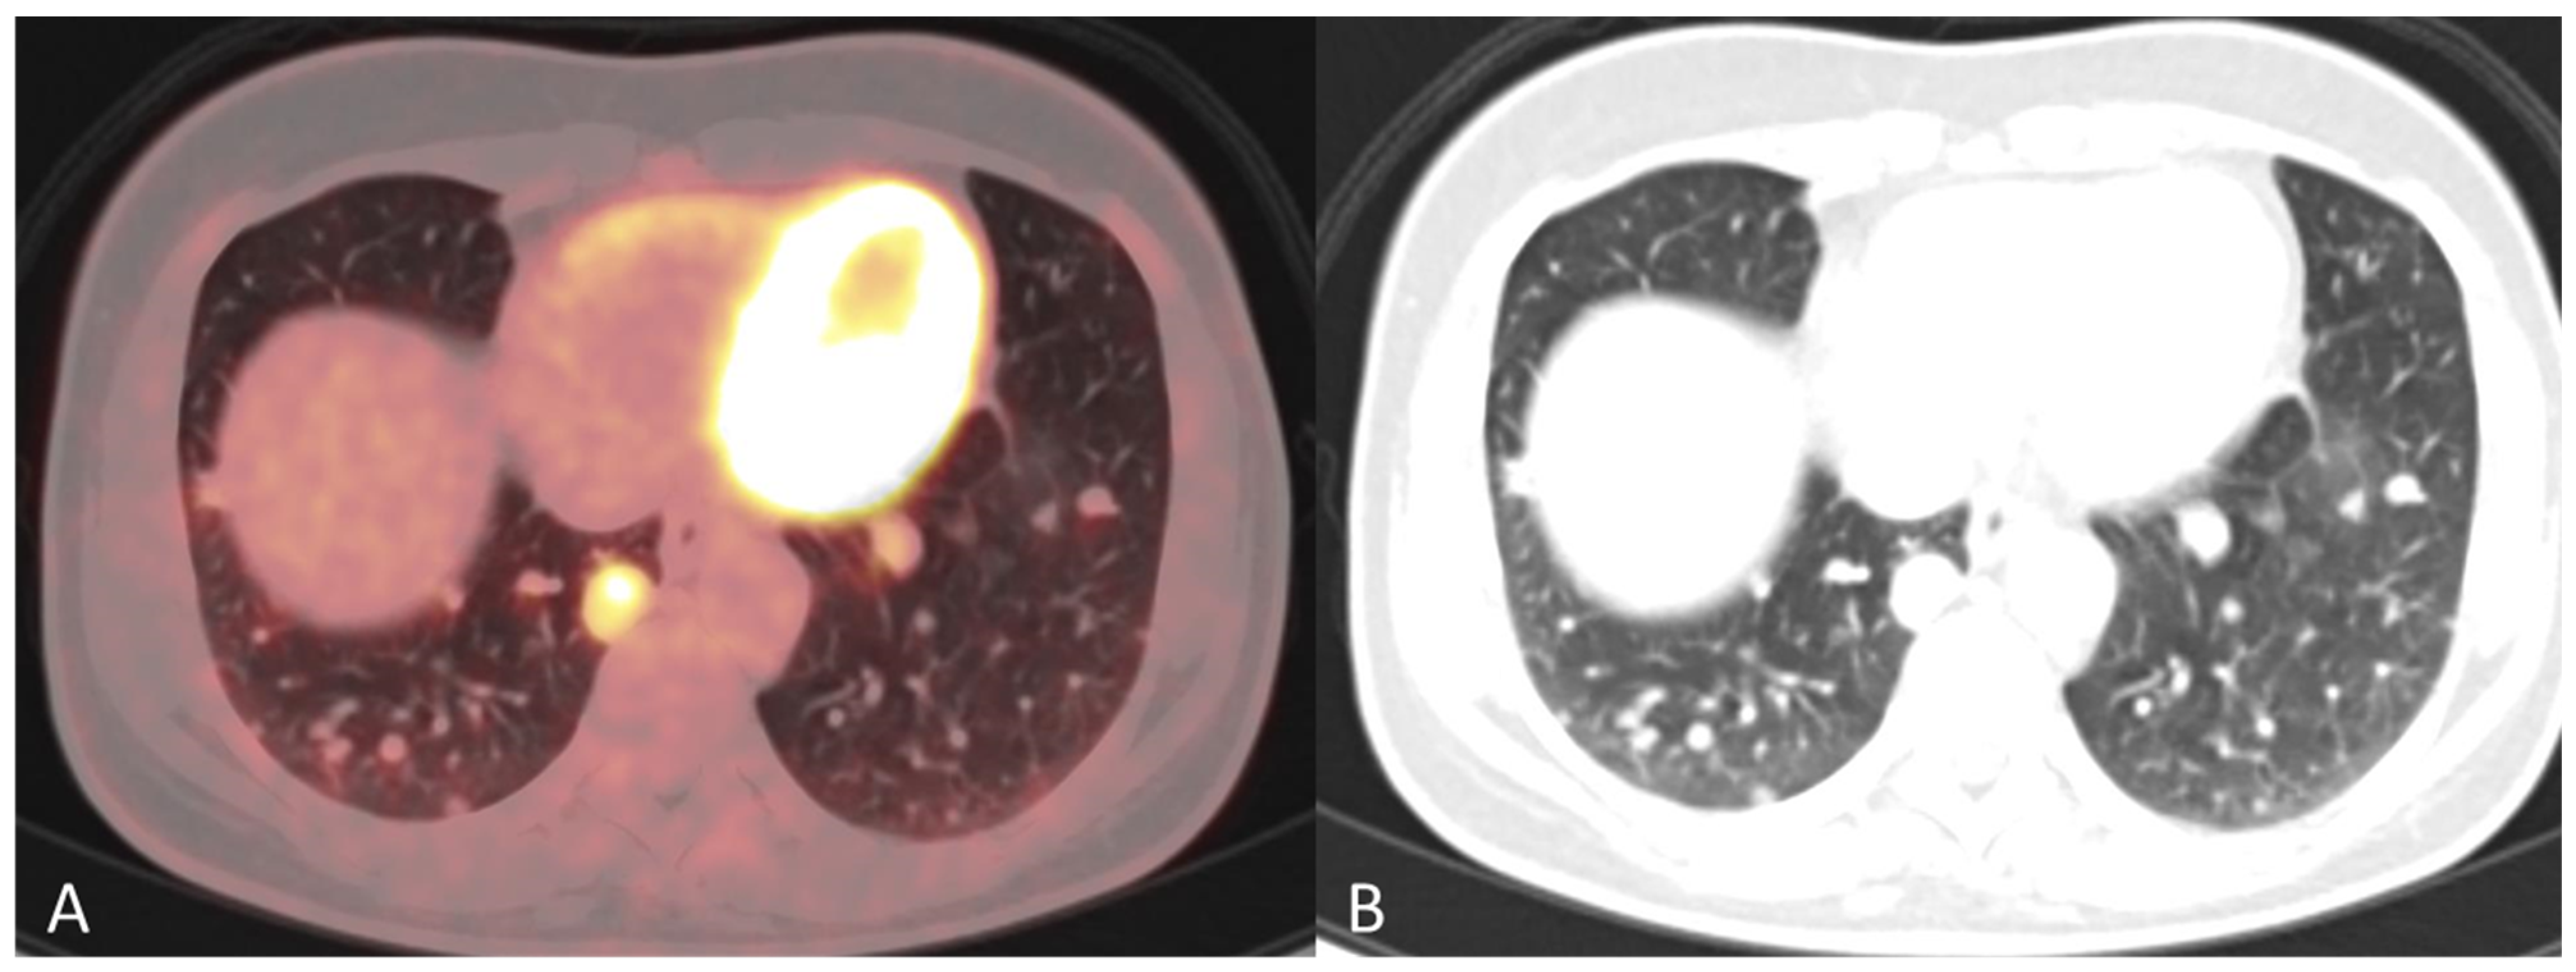

Disseminated Primary Uterine Hepatoid Adenocarcinoma with α-Fetoprotein Production Demonstrated on 18F-FDG PET/CT

Dejanovic, D.; Boennelycke, M.; Amtoft, A.G.; Christensen, C.B.; Wetterstroem, V.; Loft, A.; Noettrup, T.J. Disseminated Primary Uterine Hepatoid Adenocarcinoma with α-Fetoprotein Production Demonstrated on 18F-FDG PET/CT. Diagnostics 2022, 12, 1447. https://doi.org/10.3390/diagnostics12061447